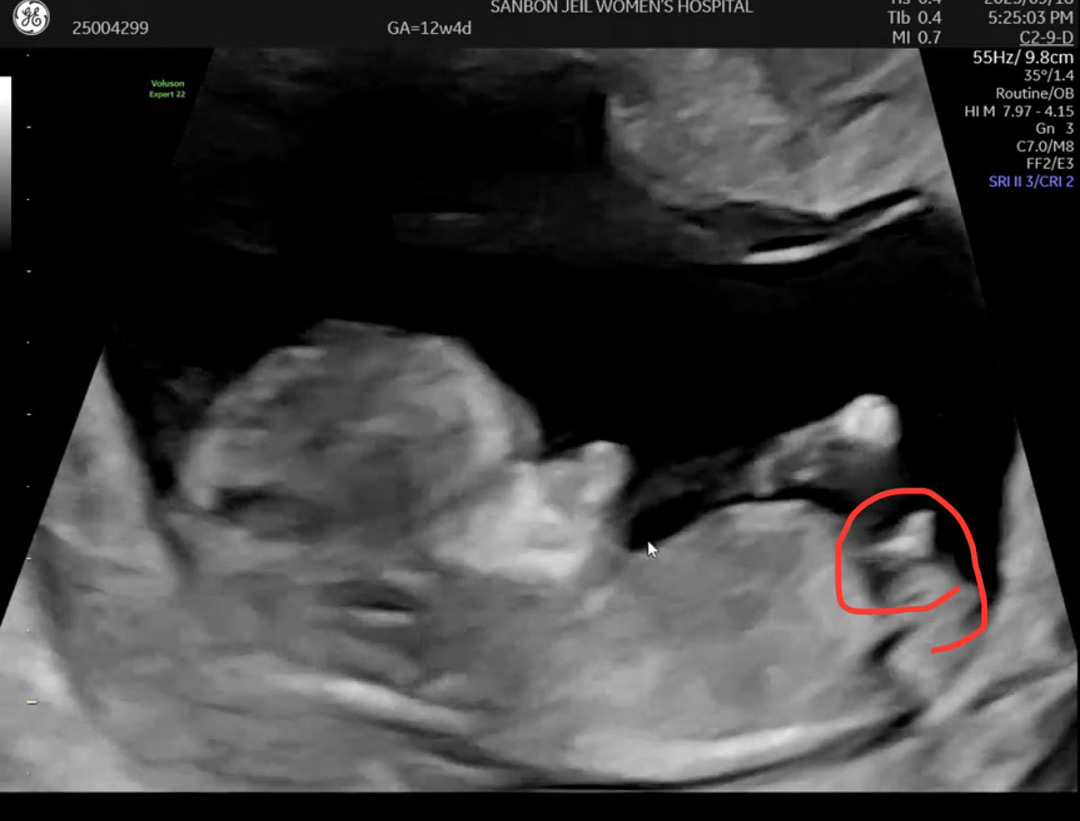

12주입니다 ㅜㅜ! 돌기가 백퍼 아들 각도법 맞죠..? 탯줄은 아니겠죠.. 허허허